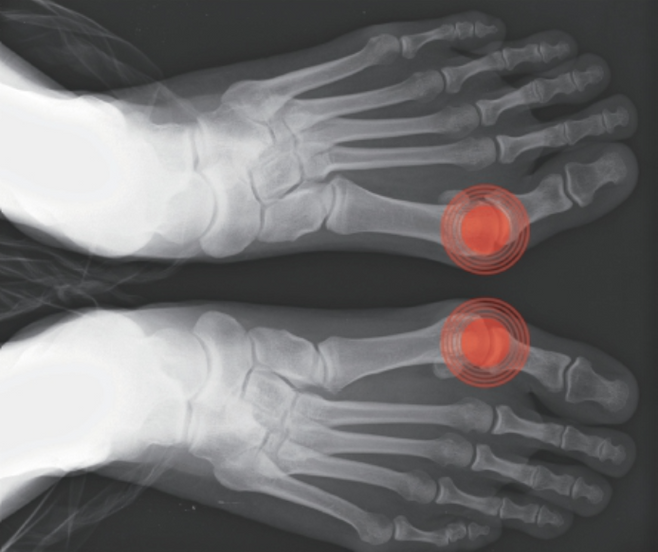

엄지발가락 끝이 두 번째 발가락 쪽으로 휘는 병을 무지외반증이라 한다. 일반적으로는 중년여성에게 많이 발생하는 것으로 알려져 있으나 어린 나이에도 발생하며 남자에게도 발생한다.

점차 발가락 휨이 진행되면 엄지발가락이 둘째 발가락 쪽으로 휘어지고 내측으로 회전되면서 제1중족지 관절이 안쪽으로 돌출되는 건막류(튀어 나옴)가 발생하는데, 장시간 서 있거나 걸어 다닐 때 튀어 나온 부위가 신발과 마찰을 일으켜 통증이나 염증을 유발하게 된다. 이에 따라 튀어나온 부위의 통증과 신발 착용에 어려움을 호소하게 되고, 발 내측면의 안정성 저하와 함께 보행 시 지면을 박차고 나가는데 중요한 역할을 하는 엄지발가락의 기능이 점차 떨어지게 된다.

무지외반증 검사로는 이학적 검사를 하고, 체중부하 전후 방사선 검사를 시행해 발가락 뼈들의 각도를 측정함으로써 초기, 중기, 말기 또는 경증, 중등도, 중증으로 구분한다. 또 혈액 검사 등 다양한 검사를 시행해 치료 방법을 결정하게 된다.